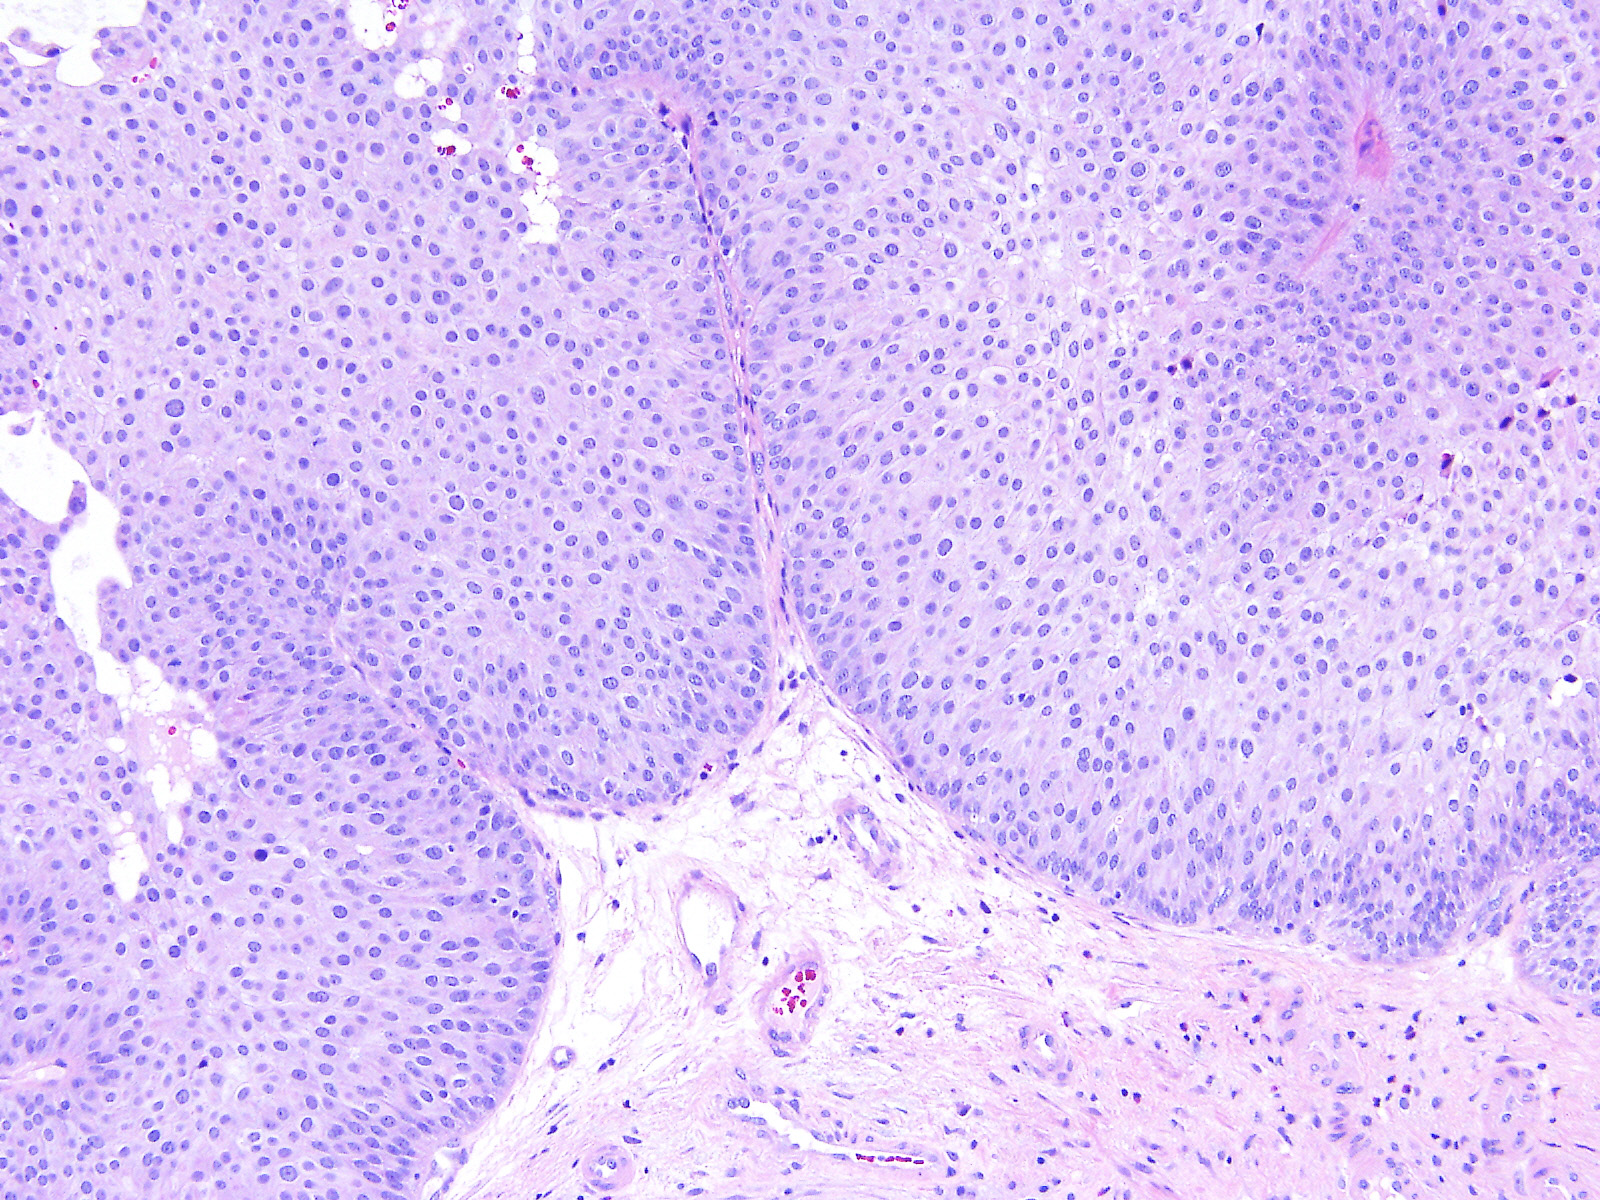

Bladder Papillary Lesions

Case ID: 526